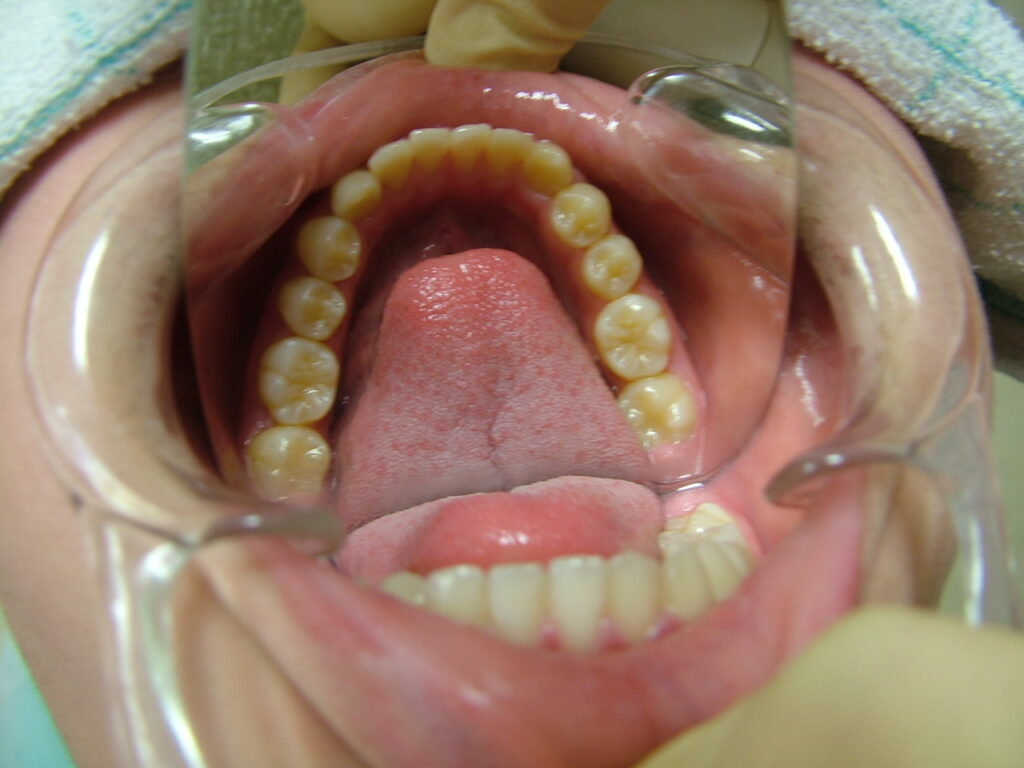

治療後

13歳頃、永久歯列になったところで、1期治療終了。後は親御さんが希望されたため、メンテナンスに移行し、高校生になったら下の親知らずを抜歯することにしました。